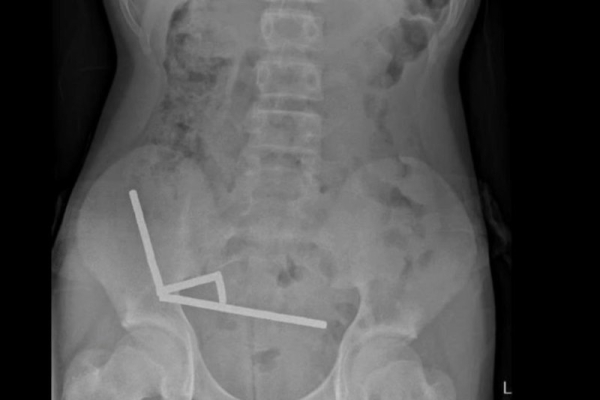

A 13-year-old boy in New Zealand needed emergency surgery and lost part of his bowel after swallowing more than 80 small, high-powered magnets, doctors said. Photo courtesy of the New Zealand Medical Journal

Scans showed that the magnets had formed four chains inside his abdomen, binding parts of the bowel together.